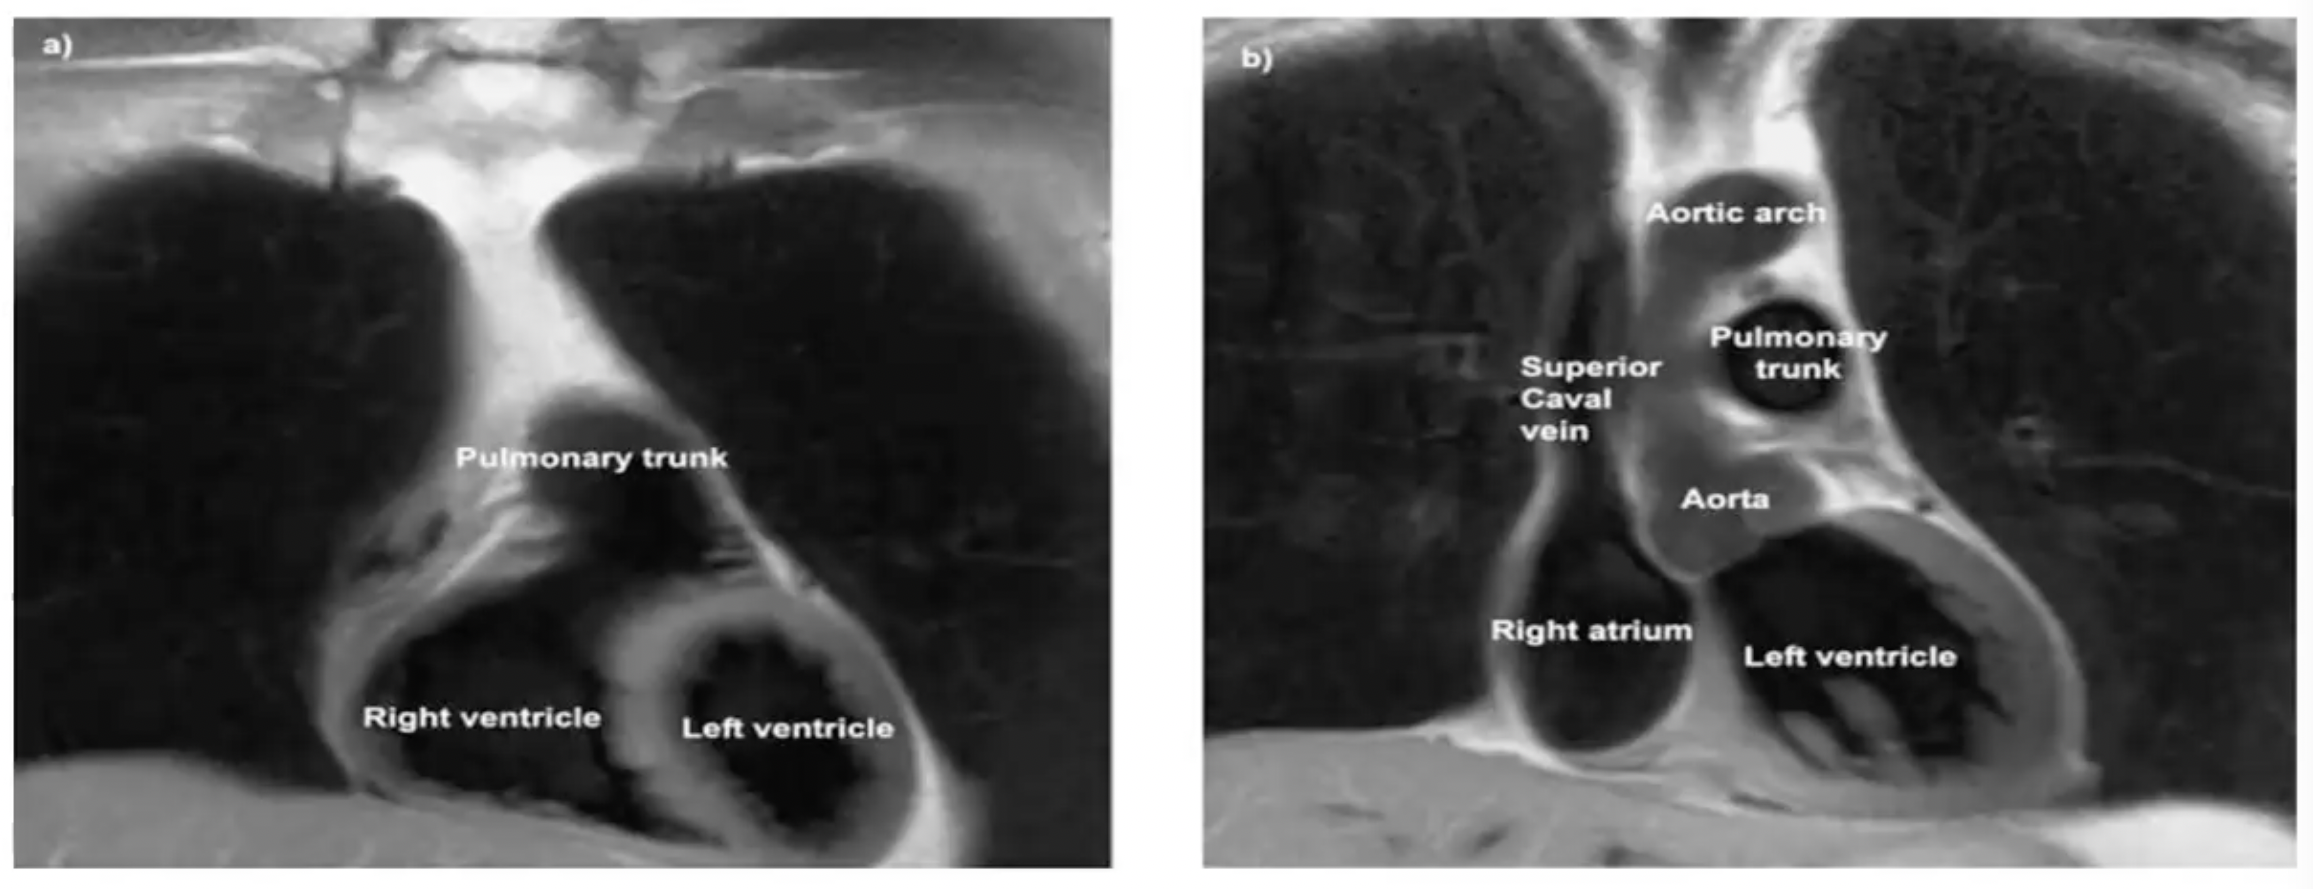

- 观察右心房、肺动脉主干、右心室

- 观察左心室、右心房、右心室、主动脉弓